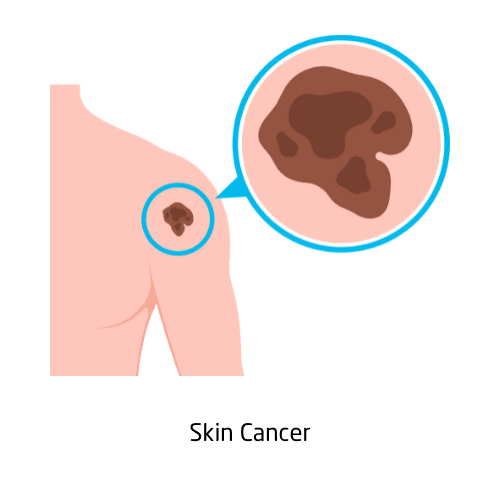

Skin cancer is the abnormal growth of skin cells, most often caused by ultraviolet (UV) exposure from the sun or tanning beds. It includes melanoma, which is the most serious form, as well as basal cell carcinoma and squamous cell carcinoma. Warning signs include new growths, changes in existing moles, or sores that don’t heal. Early detection with regular skin checks and dermatological exams can lead to high survival rates. Prevention includes sun protection, wearing SPF, and avoiding peak sun hours.

Treatments depend on type and severity, and may involve surgical removal, topical therapies, or immunotherapy.